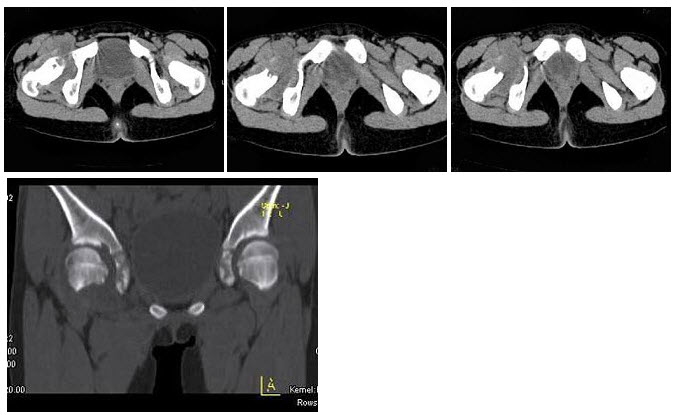

26、单项选择题

女,11岁,肺部有结核病史,二个月前右髋关节有外伤史,右髋关节部逐渐肿胀疼痛,休息后可减轻,结合图像,最可能的诊断是()

A.右髋关节结核

B.化脓性关节炎

C.右髋关节退行性变

D.右髋关节类风湿关节炎

E.右髋关节痛风